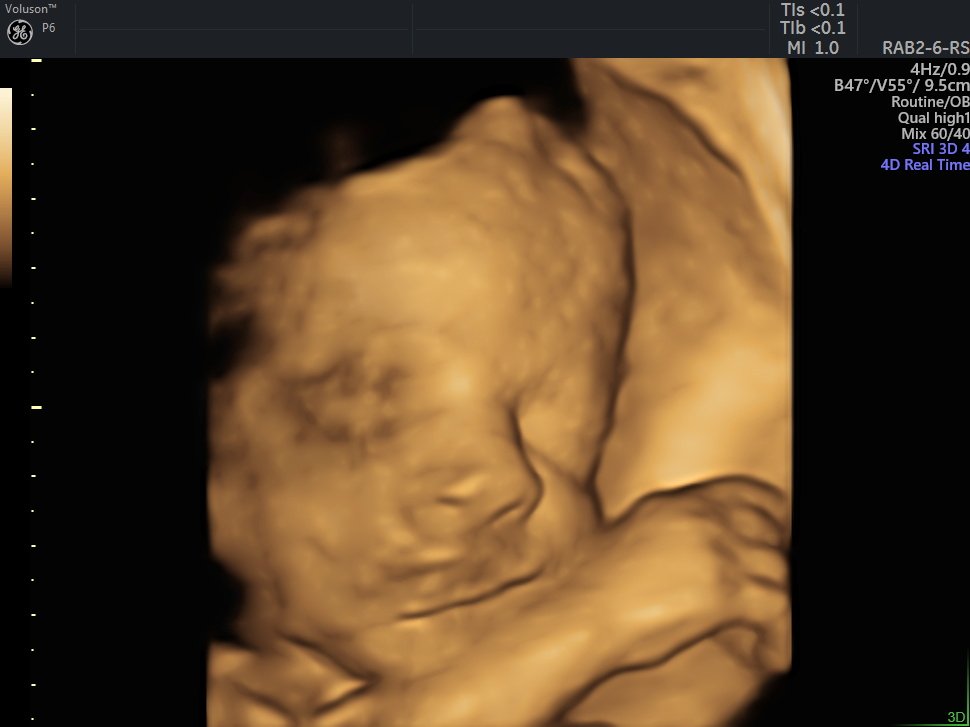

4 D Ultrasonografi

4 Boyutlu (Renkli) Ultrason ve Doppler Ultrasonografi